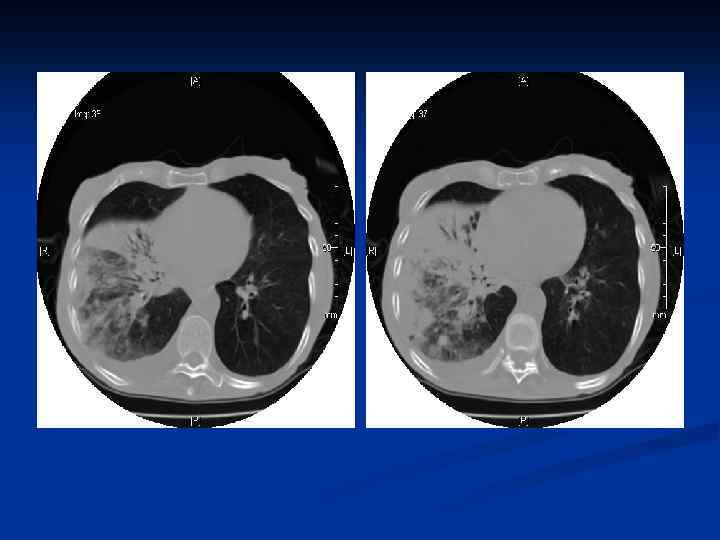

n В рентгеновском изображении хроническая пневмония выглядит как сегментарное или полисегментарное затемнение неправильной формы. Пораженный сегмент или доля обычно уменьшаются в размерах за счет фиброзирования и сморщивания. Структура пораженного участка легкого обычно неоднородна. На томограммах нередко удается обнаружить полостные образования, вызванные абсцедированием, бронхоэктазами, дистрофическими кистами, санированными абсцессами и буллезной эмфиземой.

n При бронхографии и компьютерной томографии при хроническом воспалительном процессе выявляется деформирующий бронхит и нередко бронхоэктазы. Деформирующий бронхит выражается неравномерностью просвета (чередованием участков сужения и расширения), неровностью контуров, обрубленностью бронхиальных ветвей, сближением бронхов.